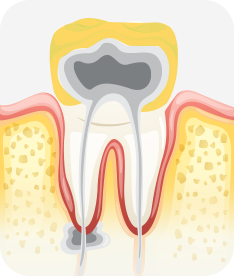

치아신경 염증

충치가 심해져 치아 뿌리까지 신경 염증이 발생함

신경소독

충치를 제거하고, 치아 뿌리 끝까지 신경관 내부의 염증 물질들을 제거하고 소독함

신경치료 완료

소독된 신경관을 생체친화적인 재료로 충전한 후 보철치료를 함